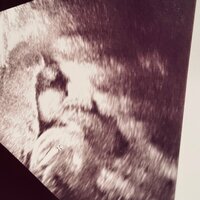

また「赤ちゃんのリズムに合わせて声がけした方が良いのかな??」「これまで通り朝昼晩、同じ時刻ぐらいに声がけしても良いのか??」と疑問を述べ「お伺いが難しい…」と悩ましい様子でコメント。最後に、前日のエコー写真とともに「これって指しゃぶりですよね?!」と問いかけ、ブログを締めくくった。